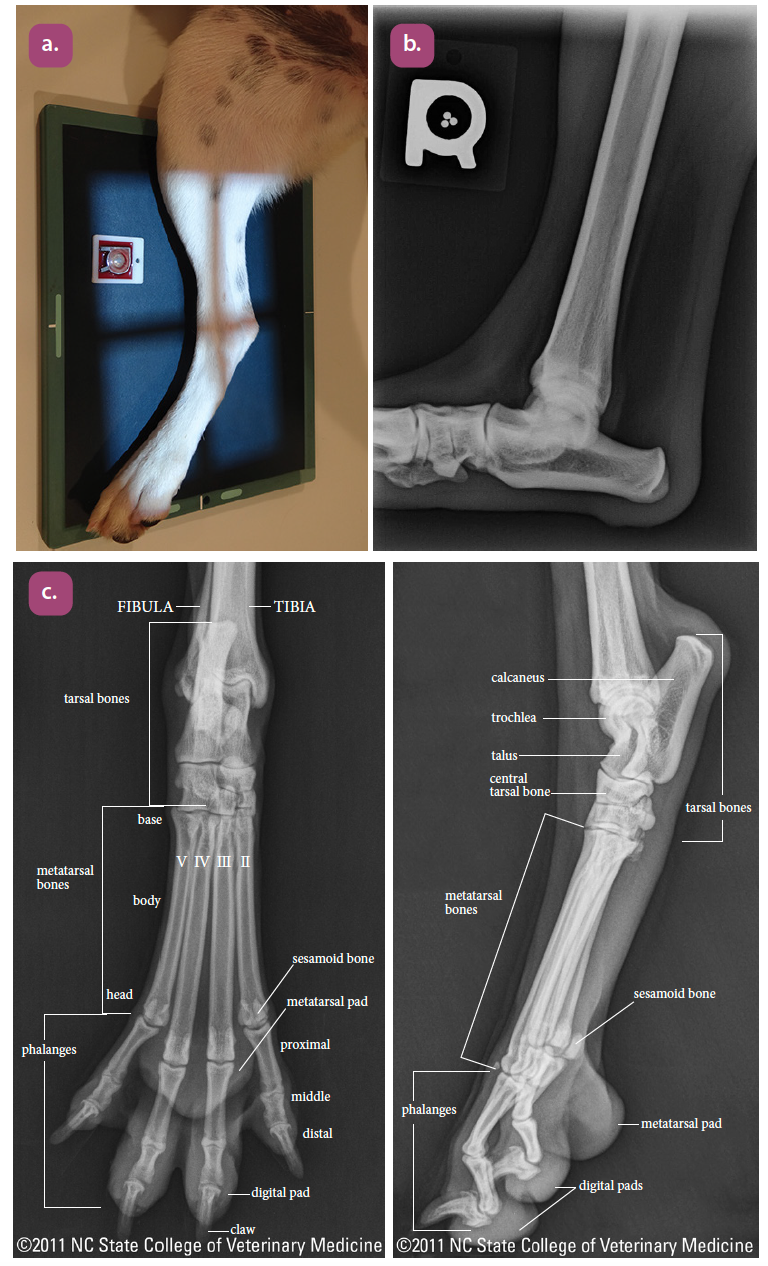

mediolateral projection of the tarsus

dorsoplantar projection of the tarsus